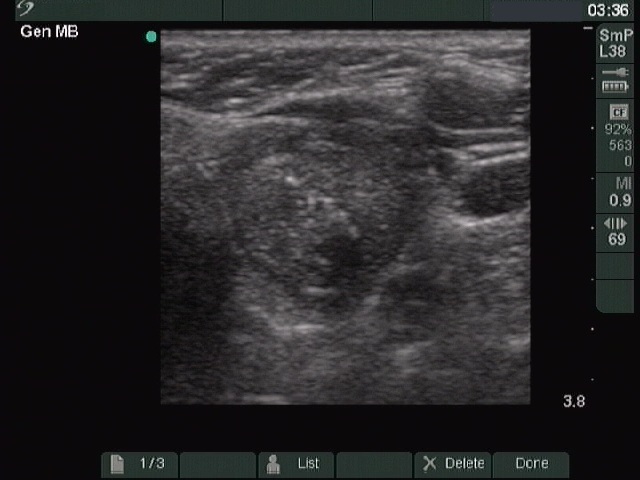

First examination (first row of images):

Clinical presentation: A 56-year-old woman known harboring an autonomously functioning adenoma requested a second opinion. The thyroid problem was known for more than ten years and caused neither hyperthyroidism nor problems. She underwent an ultrasound examination when she was told that her nodule is very suspicious because of the presence of microcalcifications.

Ultrasonography. The thyroid was echonormal. There was a small hypoechogenic lesion in the right lobe while a nodular area in the left lobe. The latter had an upper, solid part and a lower, cystic part. The former presented echogenic granules and lines.Aspiration cytology was performed from the solid part and resulted in benign lesion.